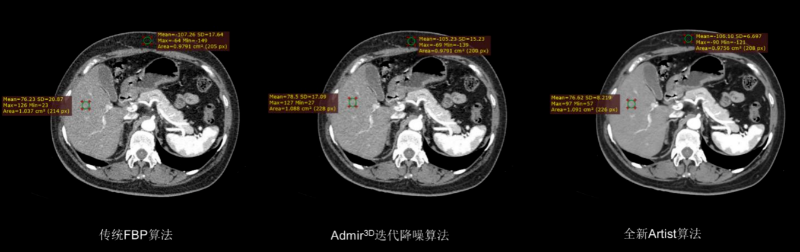

该设备集 “超高清成像、低剂量防护、极速扫描”于一体,将为辖区居民提供更精准、更安全、更便捷的诊断服务,标志着石岩人民医院在医学影像领域的诊疗水平迈入新阶段。 作为临床诊断的 “眼睛”,ANATOM X980的三大核心功能,直击患者就医痛点与临床诊断需求。 人性化设计与智能定位系统 ANATOM X980配备80厘米宽大机架孔径,结合舒缓氛围灯光,有效缓解患者检查时的紧张情绪。 设备搭载四块大尺寸高清触控屏,方便技师多角度掌握患者信息与设备状态,并可通过按键与无线遥控实现灵活摆位,大幅降低操作负荷,提升检查效率。 利用深度双目视觉认知系统,采用深度学习方式,赋予设备认知能力和行为,使系统能智能识别人体多个定位点,并在智能触屏终端上显示扫描部位,同时还能够自动识别拟扫描部位的等中心位置,实现精准化、智能化的患者摆位。 宽体探测器与极速扫描能力 依托16厘米宽体探测器结合0.25s的扫描速度,可实现全器官一站式扫描。 ▲ 心脏冠脉、主动脉、肺动脉联合扫描 通过AccuGating门控触发技术和 Adose mA电流调制技术和全新的算法、领先的AI成像技术手段,结合一键冠脉提取及分析、IVUS 模拟血管内超声、斑块分析、心功能分析、钙化积分分析、血管内窥镜、CT-FFR 技术,为患者带来了高成功率、高舒适度的单心跳(One-beat)心脏冠脉(CCTA)检查体验。 ▲ 心率103bpm 得益于一次单圈旋转最大16cm的覆盖范围,结合0.25s 的极快速度和安科独创的4D图像重建技术,在充分保证整个器官的各个位置数据的同时、同源、同向的条件下,实现了自由呼吸模式的肺部检查,为幼童、意识不清等患者肺部检查提供了最佳检查方式,为分析结果和治疗决策的准确性提供了保证。 高清影像与低剂量技术 ANATOM X980采用了基于深度学习技术的Artist 高保真图像降噪算法来对低剂量图像进行优化和处理。 与其他的算法相比,Artist 可以实现更彻底的噪声与图像信号分离,并确保在处理过程中图像细节信息不丢失,进而获得低剂量下高分辨的临床影像。 灌注扫描的剂量问题一直是临床中的老大难问题。ANATOM X980的超低mA采集及Artist还可在脑卒中解决方案中,可确保低剂量下获得精准的灌注数据。 此外,ANATOM X980还有其它几大独具特色的功能。 1.AI超分辨薄层重建技术(ASR) ANATOM X980搭载基于AI技术的高分辨率薄层图像重建技术(ASR=AI Super Resolution reconstruction),该技术利用神经网络处理单元通过深度学习的方式,对带有伪影的混叠投影数据进行伪影校正和重建,可显著降低混叠伪影,提高 CT 图像的分辨率,获得高分辨 0.3125mm 的超薄层图像,从而提高临床诊断准确性。 2.AccuImage 2048×2048显微成像 将图像数据量提高 16 倍,可显示和观察更多的病变影像细节。 3.AccuSpiral能谱成像 基于AI迭代重建与能谱解析技术,可定量分析组织成分,辅助肿瘤良恶性鉴别、结石成分分析及出血定位,为临床提供形态与功能融合的多维度信息。 目前,ANATOM X980 已在石岩人民医院影像科正式投入使用,从常规体检到复杂病症诊断,从成人检查到儿童诊疗,全方位满足临床需求。 石岩人民医院将以这台 “精准诊断利器” 为依托,持续提升诊疗能力,让居民在家门口即能享受到高质量医疗服务,用科技守护每一位居民的健康! 咨询电话 0755-27609000转0121 石岩人民医院放射科 石岩医院放射科现有医护42人,其中主任医师1名,副主任医师5名,中级职称24名,初级9名,助理技师、岗培各2名。 设备由数字化DR、CT、MR、DSA和骨密度仪等组成。中心设备齐全,拥有世界上先进的1.5T磁共振(MR)一台;螺旋CT3台(包括安科256排512层CT1台、安科64排128层CT1台、安科32排CT1台)。 数字减影血管造影机(DSA)1台;数字胃肠机1台;数字化DR和移动DR共6台;并配有现代化的PACS、HIS、肺结节和心脑血管AI辅助后处理诊断系统。 审核|梁雄 责编|马章林 审校|张永东 图文|郭文霞 编辑|冯丽萍 校对|吴曼莉